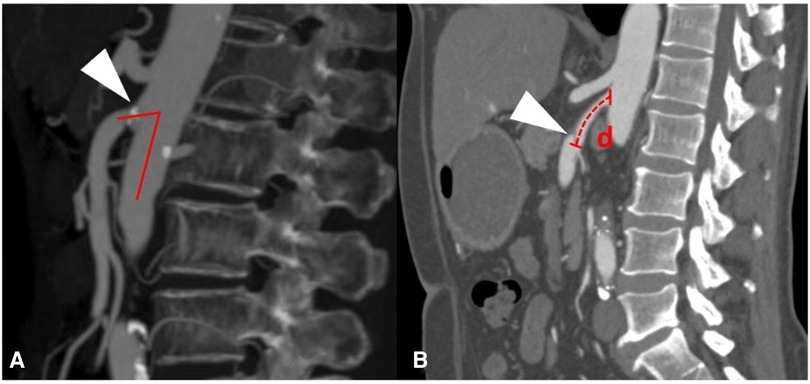

CT angiography (CTA) was performed on a 64-detector row scanner (Philips Core128, Rotterdam, The Netherlands). The scanning parameters were as follows: 120 kV; 312 mA; field of view, 362 × 362 cm; matrix, 512 × 512; and slice thickness, 0.5 mm. The locations of the plaque and dissection origins were assessed on the volume viewer using multiplanar reformatting and maximum intensity projections. The aortomesenteric angle was defined as the angle between the abdominal aorta major axis and the SMA ostium major axis (Figure 1A). The aortomesenteric angle and SMA-related distances were measured based on CTA findings (Figure 1B). All images were analyzed separately by 2 independent radiologists, both with >10 years' experience in vascular radiology. The measurements were repeated 20 days later, and the mean of the 2 sets of values was used for analysis.

Figure 1. Measurements obtained using findings from computed tomography angiography. (A) Measurement of the aortomesenteric angle (red lines) and location of the superior mesenteric atherosclerotic plaque (white arrow). (B) Measurement of the distance (red d) from the root of the superior mesenteric artery to the origin of the superior mesenteric artery dissection (white arrow).